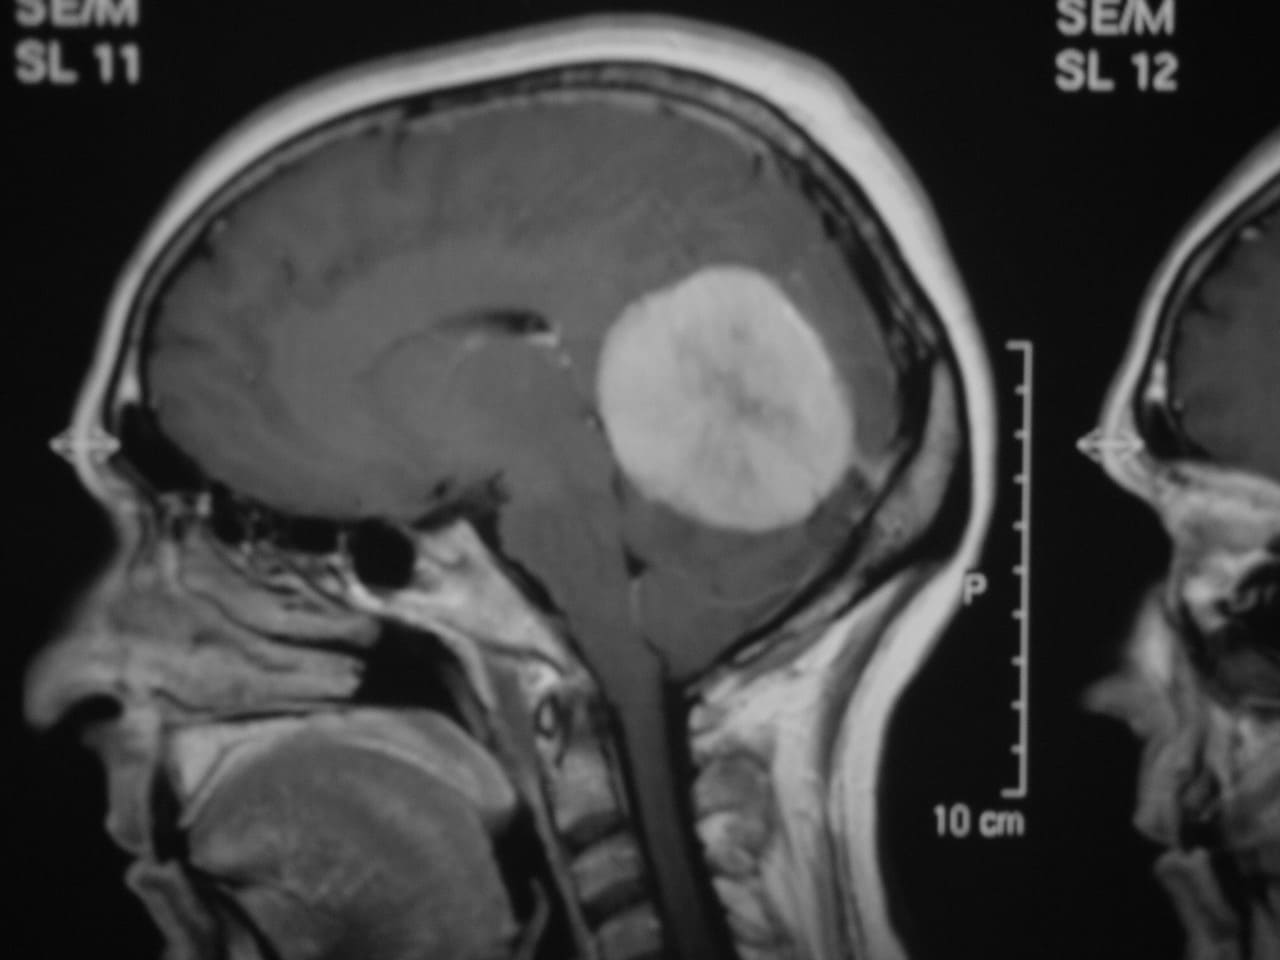

El diagnóstico se puede confirmar y el tumor localizar mediante:

• RM cerebral